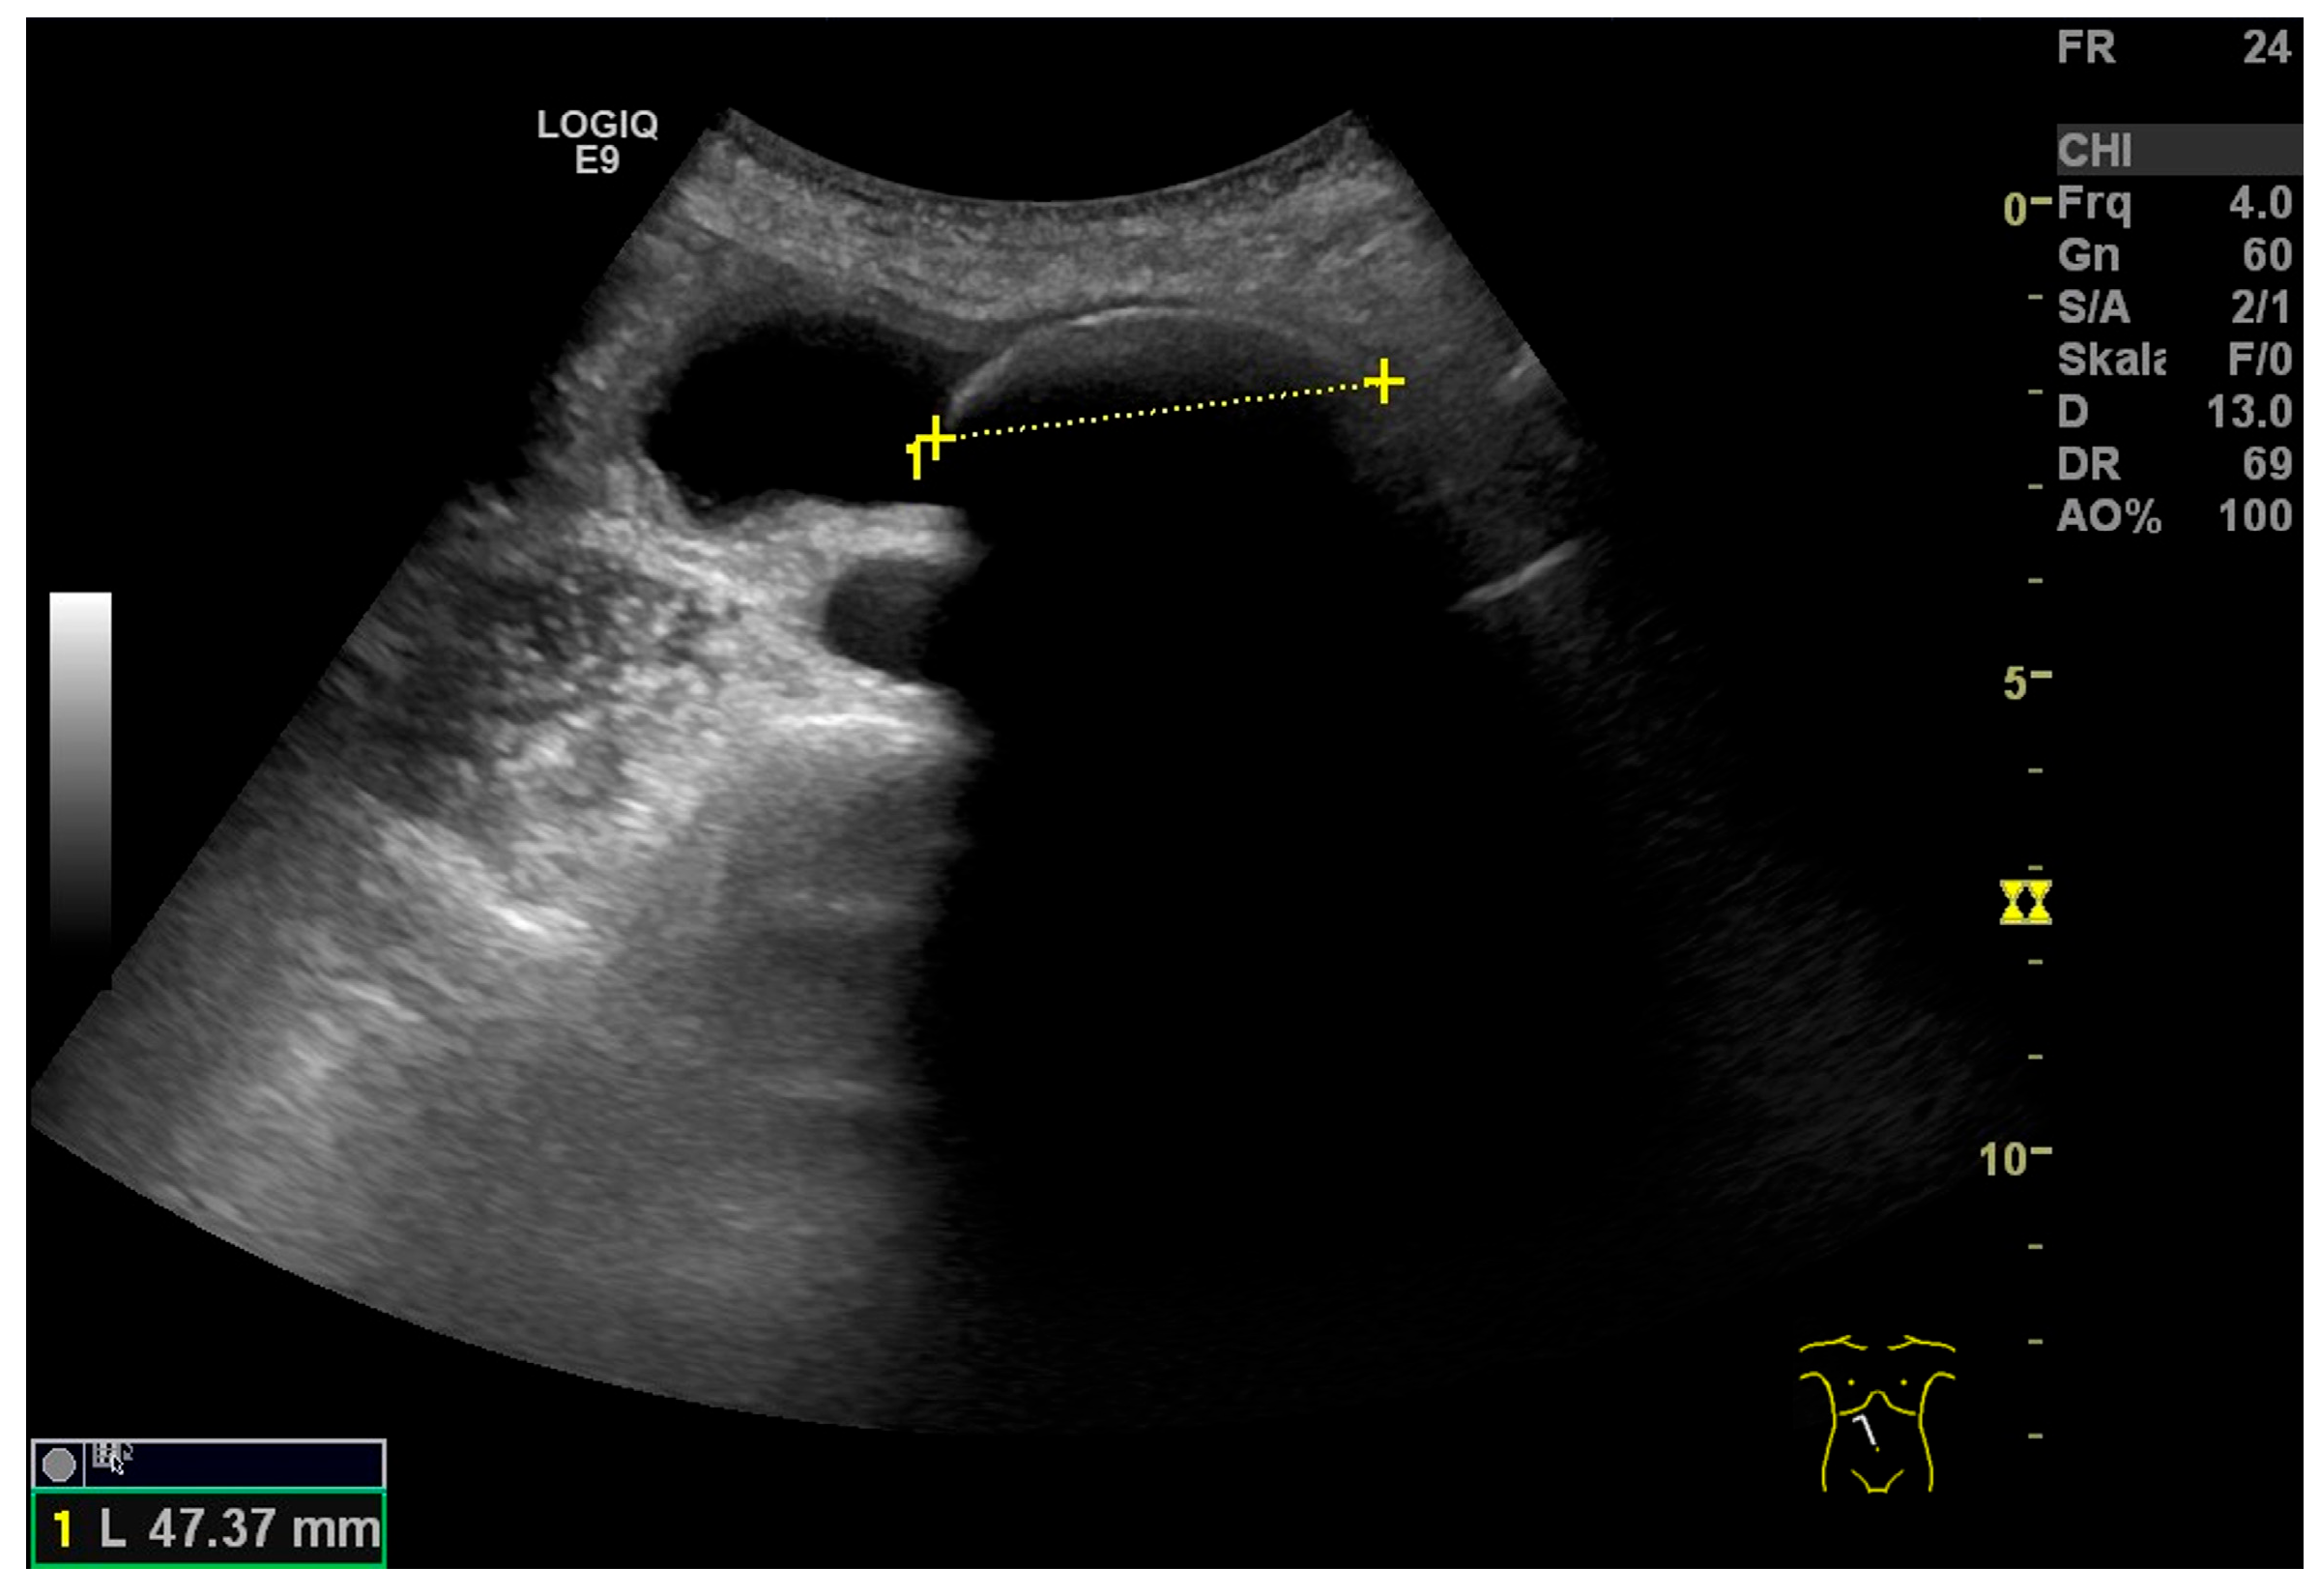

3.1. Gallbladder Size (Length and Width)

4.5. Gallbladder Hydrops